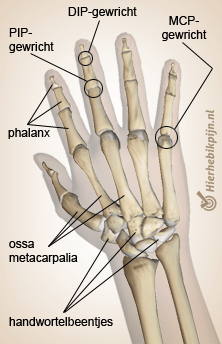

Hand en vingers